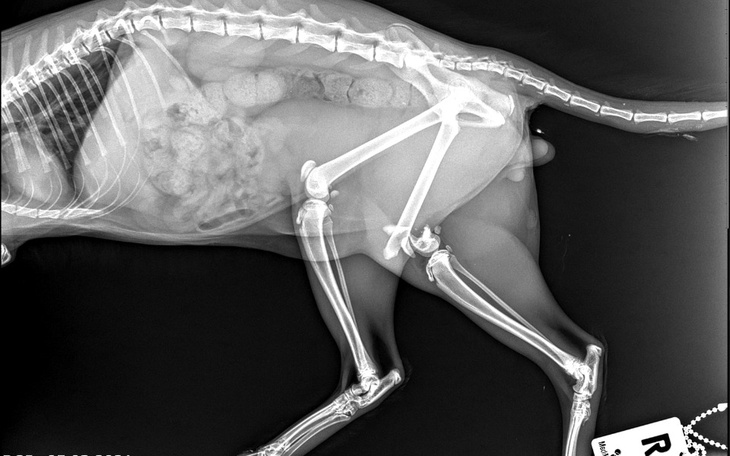

Wczoraj, 12 marca, Staś trafił do kliniki weterynaryjnej Centrum w Bydgoszczy. Oględziny, prześwietlenie rtg i natychmiastowa decyzja o operacji. "Złamanie nasady dalszej kości udowej prawej z odłamem pośrednim. Złamanie repozycyjne. Repozycja i stabilizacja przy pomocy dwóch gwoździ Kirchnera 1.5 i drutu ortopedycznego."